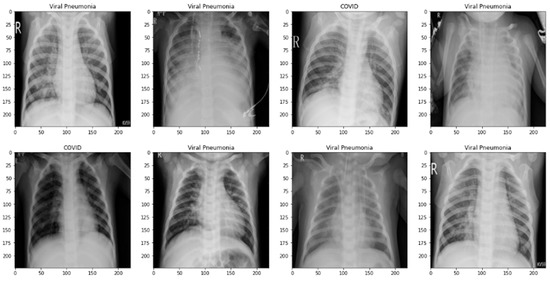

3.2.1. Pre-Processing Steps

3.2.2. Data Augmentation to Control Class Imbalance